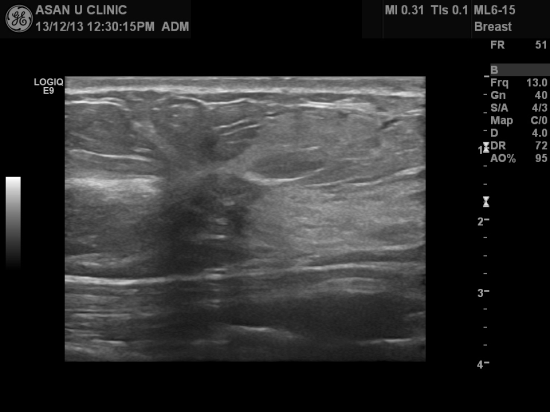

아산유외과 개원 후 45번째 유방암진단.

우측 유방에 만져지는 멍우리 있어 내원하신 50세 여성분입니다.

1.52cm의 결절있어 조직검사하였고 침윤성 유방암으로 진단 되셨습니다.

우리나라 여성의 대부분은 40대에서 50대에 유방암이 진단됩니다.

만져지는 혹이 없고 가족력이 없더라도

유방이 정상인지 점검해보실 필요가 있습니다.